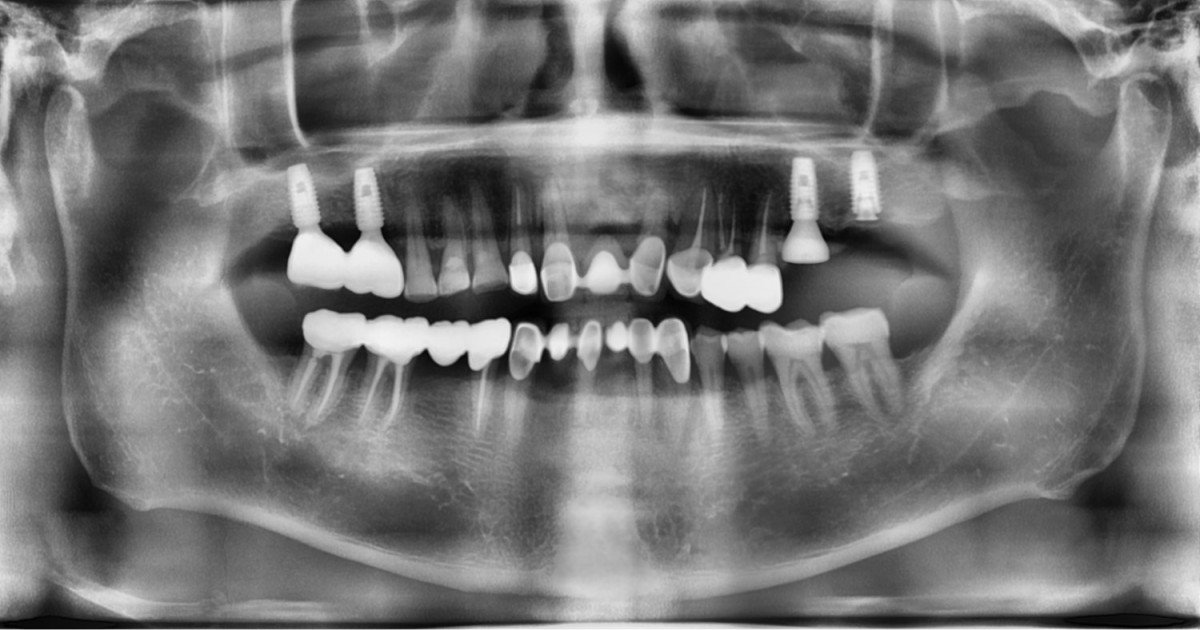

A 57-year-old male patient recently underwent

implant restoration on the maxillary right molar. This time, he is scheduled to

proceed with the left molars. (ARUM implant system)

▲2 implants were placed. ArumDentistry NB1 5*10 (30Ncm) in the 1st molar and 5*10 (10Ncm) in the 2nd molar.